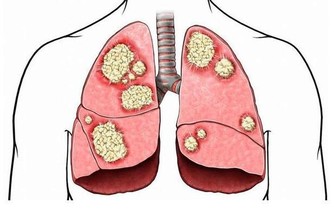

5、自己亂吃藥

不少非處方藥也有一定的毒性,最常見的是人們感冒後自行服用的抗生素、解熱鎮痛藥等,比較敏感的人可能因此引起腎功能不全或急性腎衰。(詳情可戳→最傷肝傷腎的一件事,很多人沒在意!有人因此付出慘痛代價)

而且腎損傷早期的表現都比較輕微,容易被忽視而發展成慢性腎病。

所以,沒事建議別亂吃藥,而吃藥期間一旦出現小便異常、血壓升高、四肢水腫、腰酸乏力等情況,可能提示急性腎損傷,應馬上就診。希望今天分享的文章,能夠幫助到更多的朋友~謝謝您。